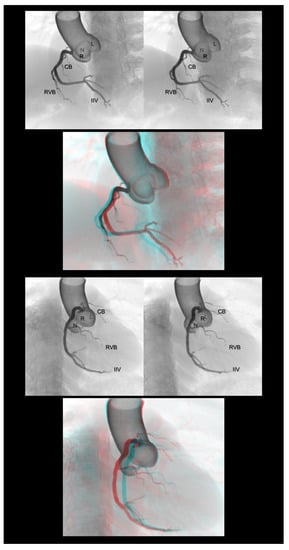

4.4. Pulmonary Arteries

4.5. Valvar Heart Diseases